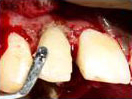

Labial Soft Tissue

Reflected

Tooth with Fracture Extending Sub-Gingivally

Palatal Soft Tissue

Splinting of Fracture

Fragments with direct

Composite Veneering